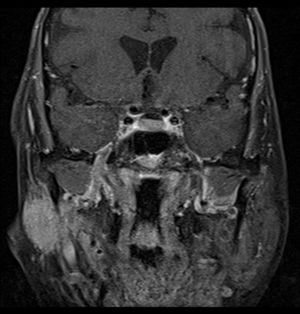

침샘암은 침샘에 발생하는 종양으로, 덩어리나 부기를 동반하며, 초기에는 양성 종양과 구별이 어려울 수 있다. 진단은 신체 검사, 내시경, MRI 또는 CT 스캔, 생검 등을 통해 이루어진다. 치료는 수술이 주를 이루며, 방사선 치료, 화학 요법, 표적 치료가 사용될 수 있다. 침샘 종양의 대부분은 양성이며, 발생률은 드문 편이다.

침샘암 진단에는 다양한 방법이 사용된다. 신체 검사 및 병력 청취를 통해 전반적인 건강 상태를 확인하고, 내시경 검사로 입 안, 인후 등을 관찰한다. 또한, MRI, CT, 방사선 사진, 초음파와 같은 영상 검사를 통해 종양 유무 및 전이 여부를 확인하며, 필요한 경우 생검을 실시하여 암세포를 확인한다.

3. 3. 영상 검사